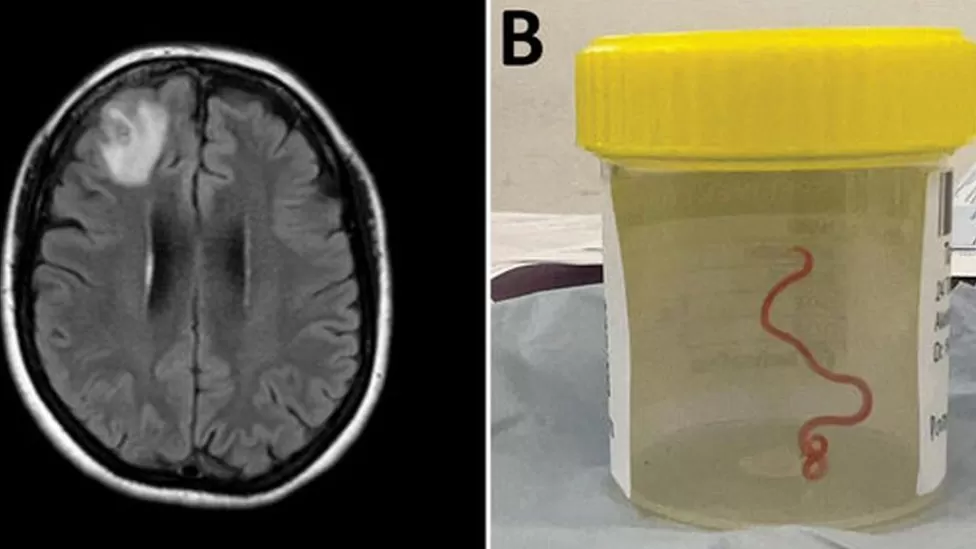

The patient was admitted to hospital in late January 2021. A scan later revealed “an atypical lesion within the right frontal lobe of the brain”. The cause of her condition was only revealed by a surgeon's knife during a biopsy in June 2022.